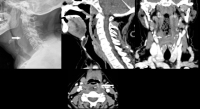

Ingresan inmediatamente a paciente con absceso retrofaríngeo en el Hospital General de Tuxtepec

La paciente, quien fue auxiliada en vía pública por paramédicos, ingresó con un diagnóstico de diabetes mellitus tipo II y un absceso retrofaríngeo con varios días de evolución, sin tratamiento previo. Debido a la gravedad del cuadro clínico, se procedió de manera inmediata a su ingreso al área de urgencias, donde fue atendida por personal médico especializado

Oaxaca, México. 05 mayo 2025.- Servicios de Salud de Oaxaca (SSO) informa que el pasado 3 de mayo fue recibida en estado grave en el Hospital General de Tuxtepec una paciente de 39 años de edad, originaria de la localidad de San Martín Caballero, municipio de San José Tenango, en atención a una llamada al número de emergencia 9-1-1.

La paciente, quien fue auxiliada en vía pública por paramédicos, ingresó con un diagnóstico de diabetes mellitus tipo II y un absceso retrofaríngeo con varios días de evolución, sin tratamiento previo. Debido a la gravedad del cuadro clínico, se procedió de manera inmediata a su ingreso al área de urgencias, donde fue atendida por personal médico especializado.

Posteriormente, fue intervenida quirúrgicamente en un intento por controlar la infección y preservar su vida. Lamentablemente, y pese a los esfuerzos realizados por el equipo médico multidisciplinario, la paciente falleció el 4 de mayo a las 16:00 horas.

SSO reitera su compromiso con la atención oportuna y profesional a todas las personas que acuden a las unidades médicas.